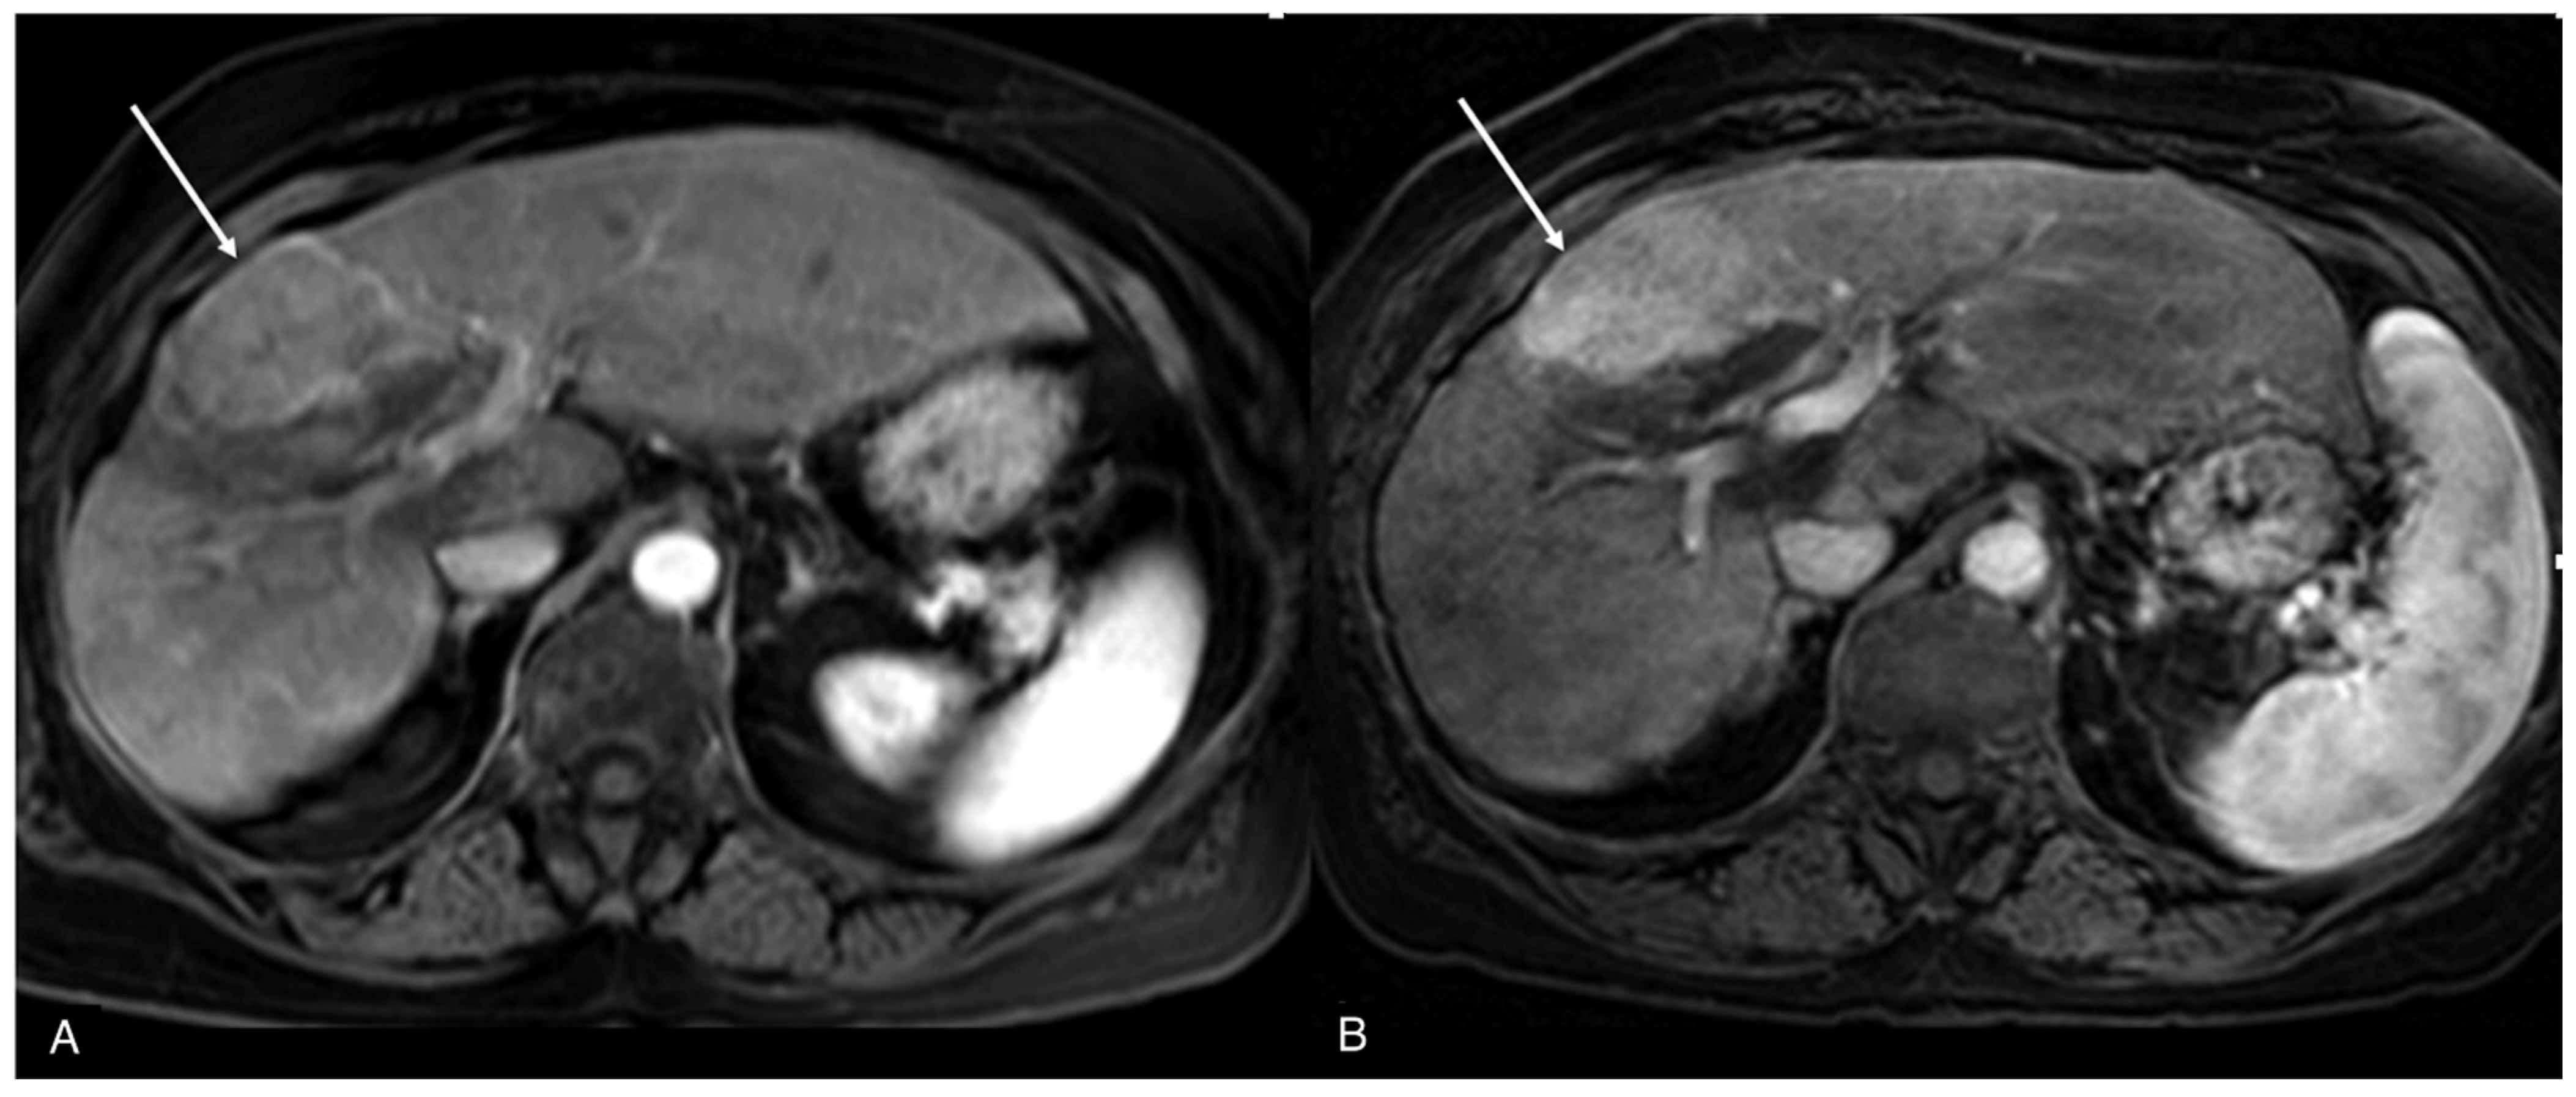

Figure 2. MRI of the same focal liver lesion ((A,B), arrows) on post-contrast T1w image at 1.5 T (A) and 3 T (B).